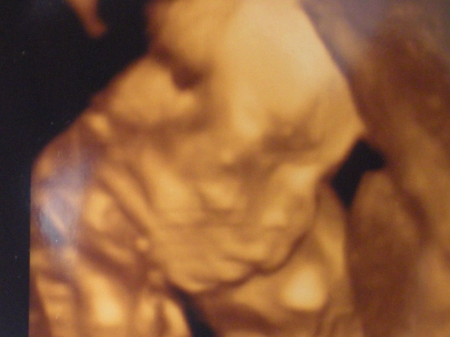

Na vyšetření ultrazvukem vám rádi vytisknou obrázek vašeho miminka!

Sonogram plodu ve 20. týdnu těhotenství: zavřená očička (víčka jsou dosud srostlá) a pootevřená pusinka navozují dojem, že je plod ospalý a zívá.

Nastává období druhého ultrazvukového vyšetření, které slouží k odhalení vývojových vad plodu. Zvláště podrobně se zkoumá srdce, ale i ostatní orgány. Ve 20. týdnu těhotenství mohou poprvé i prvorodičky začít vnímat pohyby miminka. Dolní končetiny miminka dohnaly vývojem ty horní, usilovně kopou, což zpočátku maminka vnímá jako lechtání nebo bublání. Na povrchu těla má miminko stále jemné chloupky, na dlaních a chodidlech se rýsují kožní rýhy, unikátní znak pro každého jedince. V těchto týdnech vznikají na ultrazvuku ty nejkurióznější fotky z celého těhotenství. JM